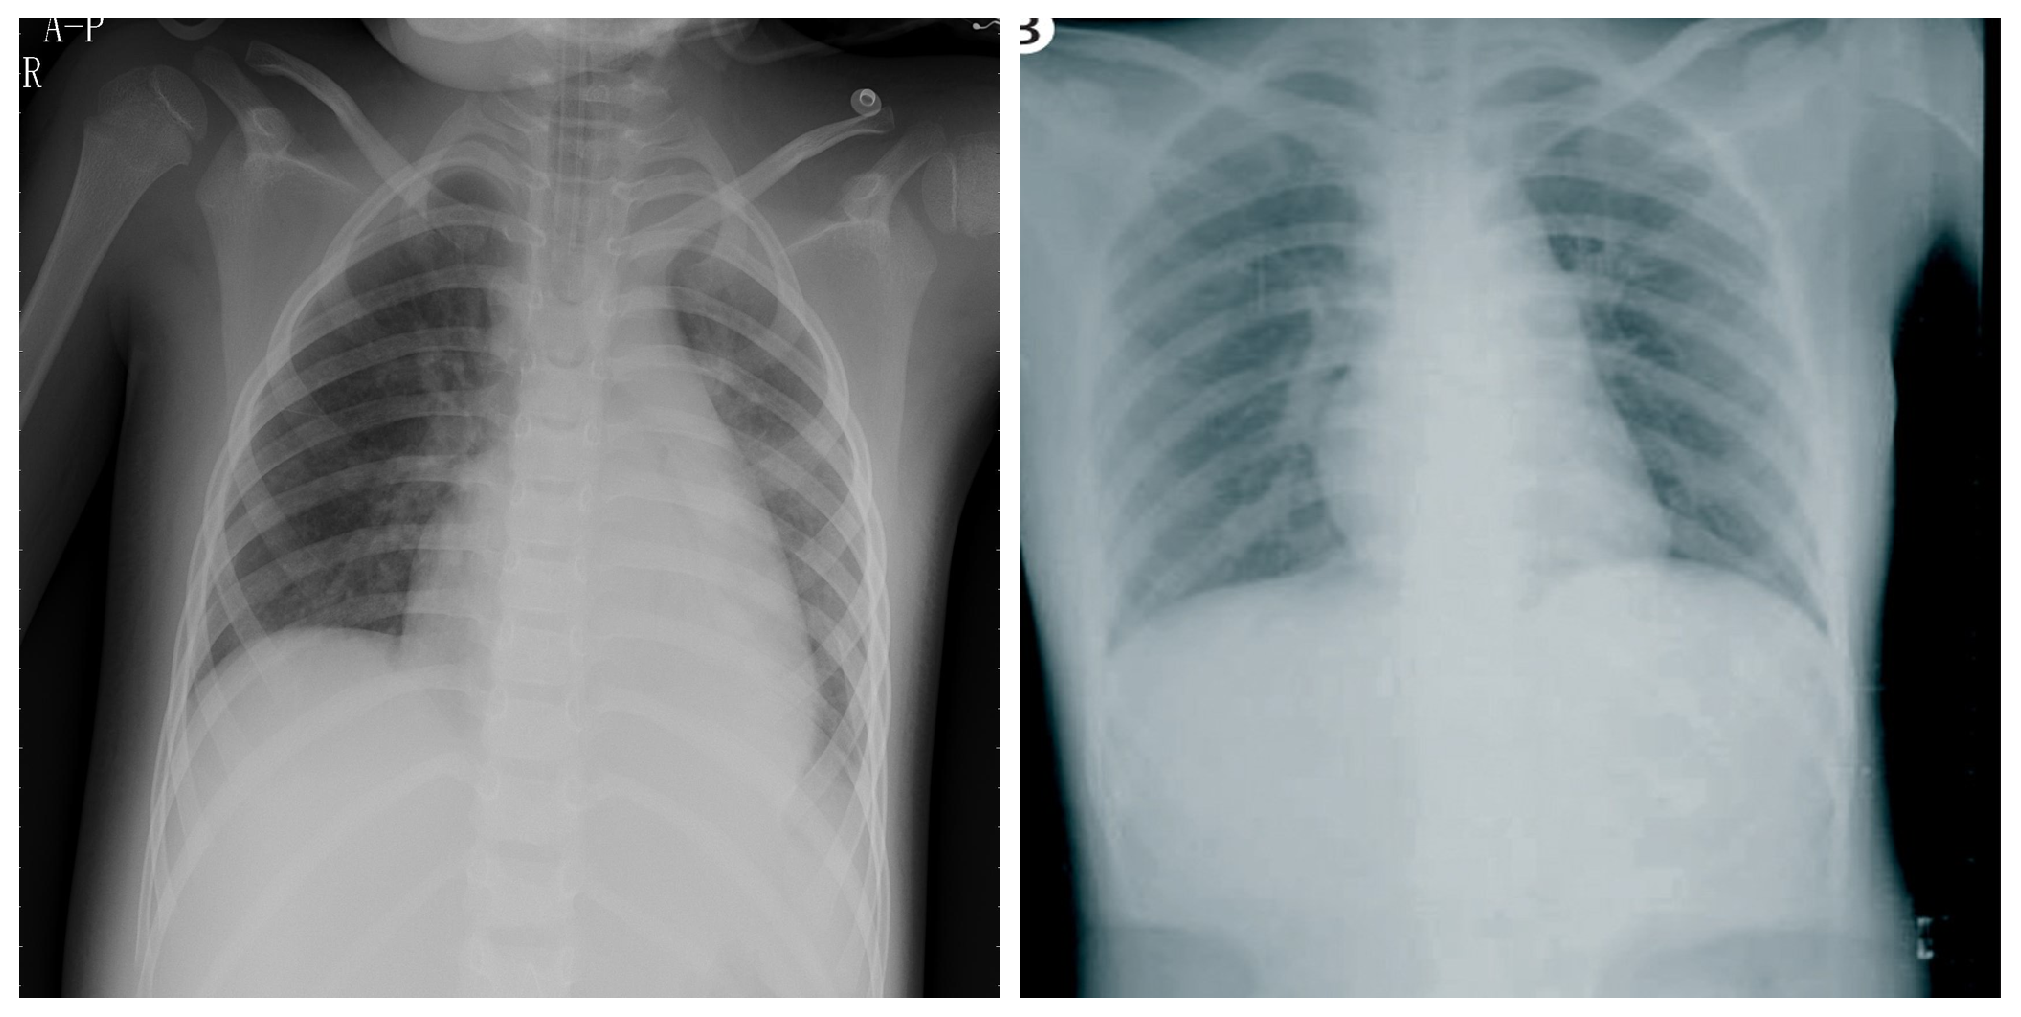

4.5. Explainability